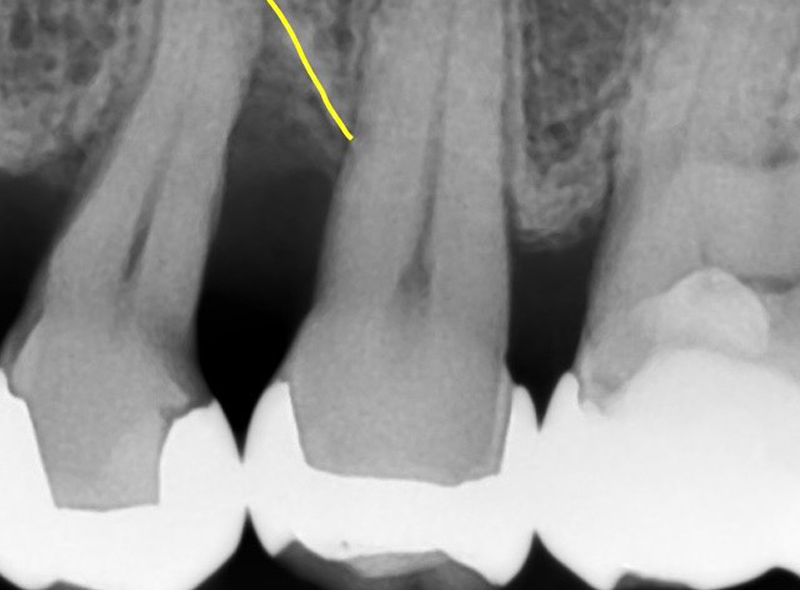

01

治療前

重度の歯周病により、歯を支える骨(歯槽骨)がV字型に失われている状態です。

-

02

治療後

治療前の点線の位置から、治療後に実線のラインまで再生されたことを示しています。

| 治療内容 | 重度の歯周病により失われた歯槽骨(歯を支える骨)に対し、歯周組織再生療法(エムドゲインゲル使用)を行い、骨組織の再生を促した。 |

|---|---|

| 治療期間 | 処置約2時間、術後メインテナンス2ヶ月 |

| 費用 | 143,000円(処置88,000円+エムドゲイン薬剤22,000円+骨補填材33,000円) |

| 注意点 |

本治療は外科処置を伴います。 術後、一時的に腫れや痛み、歯がしみる(知覚過敏)などの症状が出ることがあります。 骨の再生量には個人差があり、期待される効果が得られない可能性もあります。 術後の口腔清掃が不十分であったり、定期的なメンテナンスを怠ったりすると、歯周病が再発するリスクがあります。 エムドゲインの特徴として口腔清掃状態が良ければ処置の効果(骨ができる可能性)が約2年続くと言われています。 |